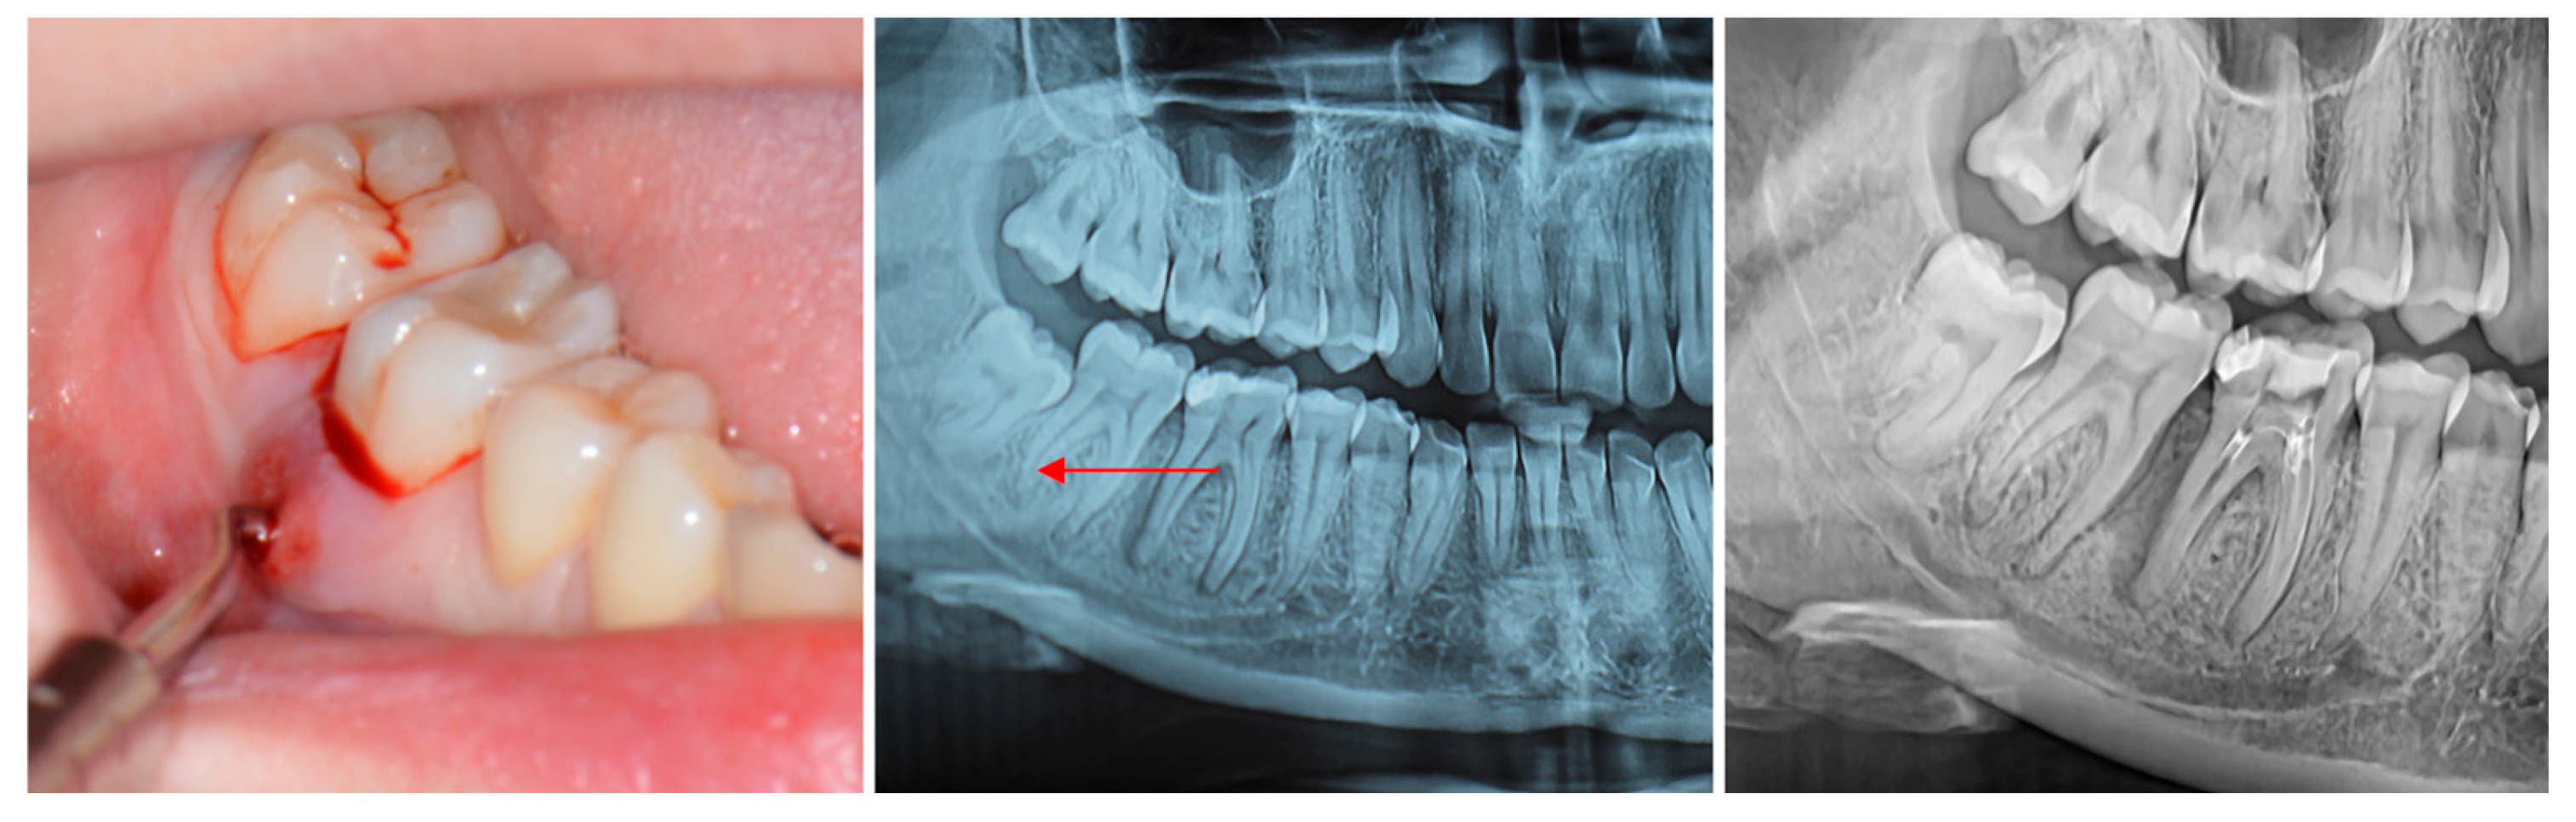

Radiographic Evaluation